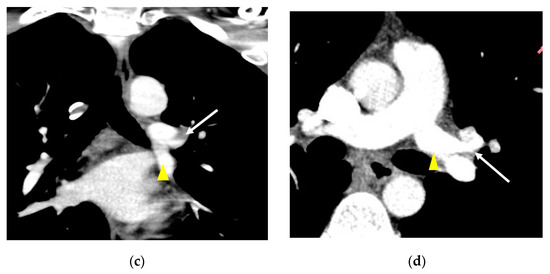

3. Results

3.1. Incidence

3.2. Lobar and Segmental Supply Patternf of the AP

3.3. Diameter of the AP

3.4. Presence of Other Accompanying Variations

4. Discussion